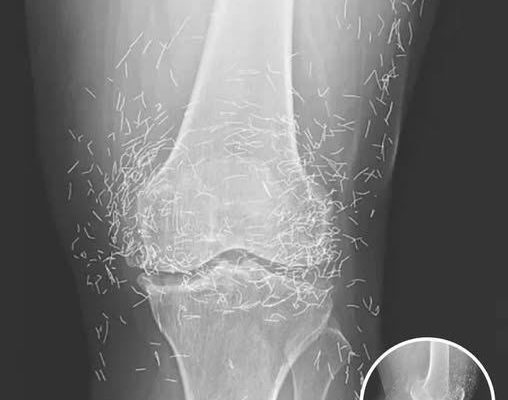

A routine X-ray revealed an unexpected surprise when doctors examined the knees of a 65-year-old woman suffering from severe joint pain. What they found was nothing short of astonishing — hundreds of tiny gold needles embedded deep in her tissue.

The woman, from South Korea, had been battling osteoarthritis for years. The painful condition breaks down cartilage and bone inside the joints, leading to stiffness and swelling. When standard treatments such as painkillers and anti-inflammatory medications failed to provide relief — and instead caused stomach problems — she turned to a popular alternative: acupuncture.

Acupuncture, a traditional therapy widely used in Asia, involves inserting thin needles into specific points on the body in an effort to relieve pain or treat illness. In this case, however, doctors say the gold needles were left behind intentionally as part of her treatment plan, designed to deliver continuous stimulation to the affected area.

There are other complications as well. Needles lodged in tissue can interfere with medical imaging. “They can obscure parts of the anatomy on an X-ray,” Guermazi noted. Even more alarming, patients with metal fragments in their bodies should never undergo an MRI, as the magnetic force could cause the needles to move — potentially puncturing blood vessels and causing life-threatening damage.

As for the South Korean woman, her case was recently documented in the New England Journal of Medicine. While the needles may have been intended to help, her X-rays tell a cautionary tale about the potential risks of extreme alternative therapies.